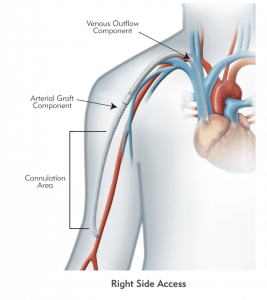

HeRO Graft (Hemodialysis Reliable Outflow) is the ONLY fully subcutaneous AV access solution clinically proven to maintain long-term access for hemodialysis patients with central venous stenosis. HeRO Graft is classified by the FDA as a graft, but differs from a conventional AV graft since it has no venous anastomosis. It consists of two primary components:

The HeRO Graft Arterial Graft Component has a 6mm inner diameter (ID), 7.4mm outer diameter (OD), and is 53cm long, inclusive of the connector. It consists of an ePTFE hemodialysis graft with PTFE beading to provide kink resistance near the proprietary titanium connector. The titanium connector attaches the Arterial Graft Component to the Venous Outflow Component. The Arterial Graft Component is cannulated using standard technique according to KDOQI guidelines.

The HeRO Graft Venous Outflow Component has a 5mm ID, 19F (6.3mm) OD, and is 40cm long. It consists of radiopaque silicone with braided nitinol reinforcement (for kink and crush resistance) and a radiopaque marker band at the distal tip.